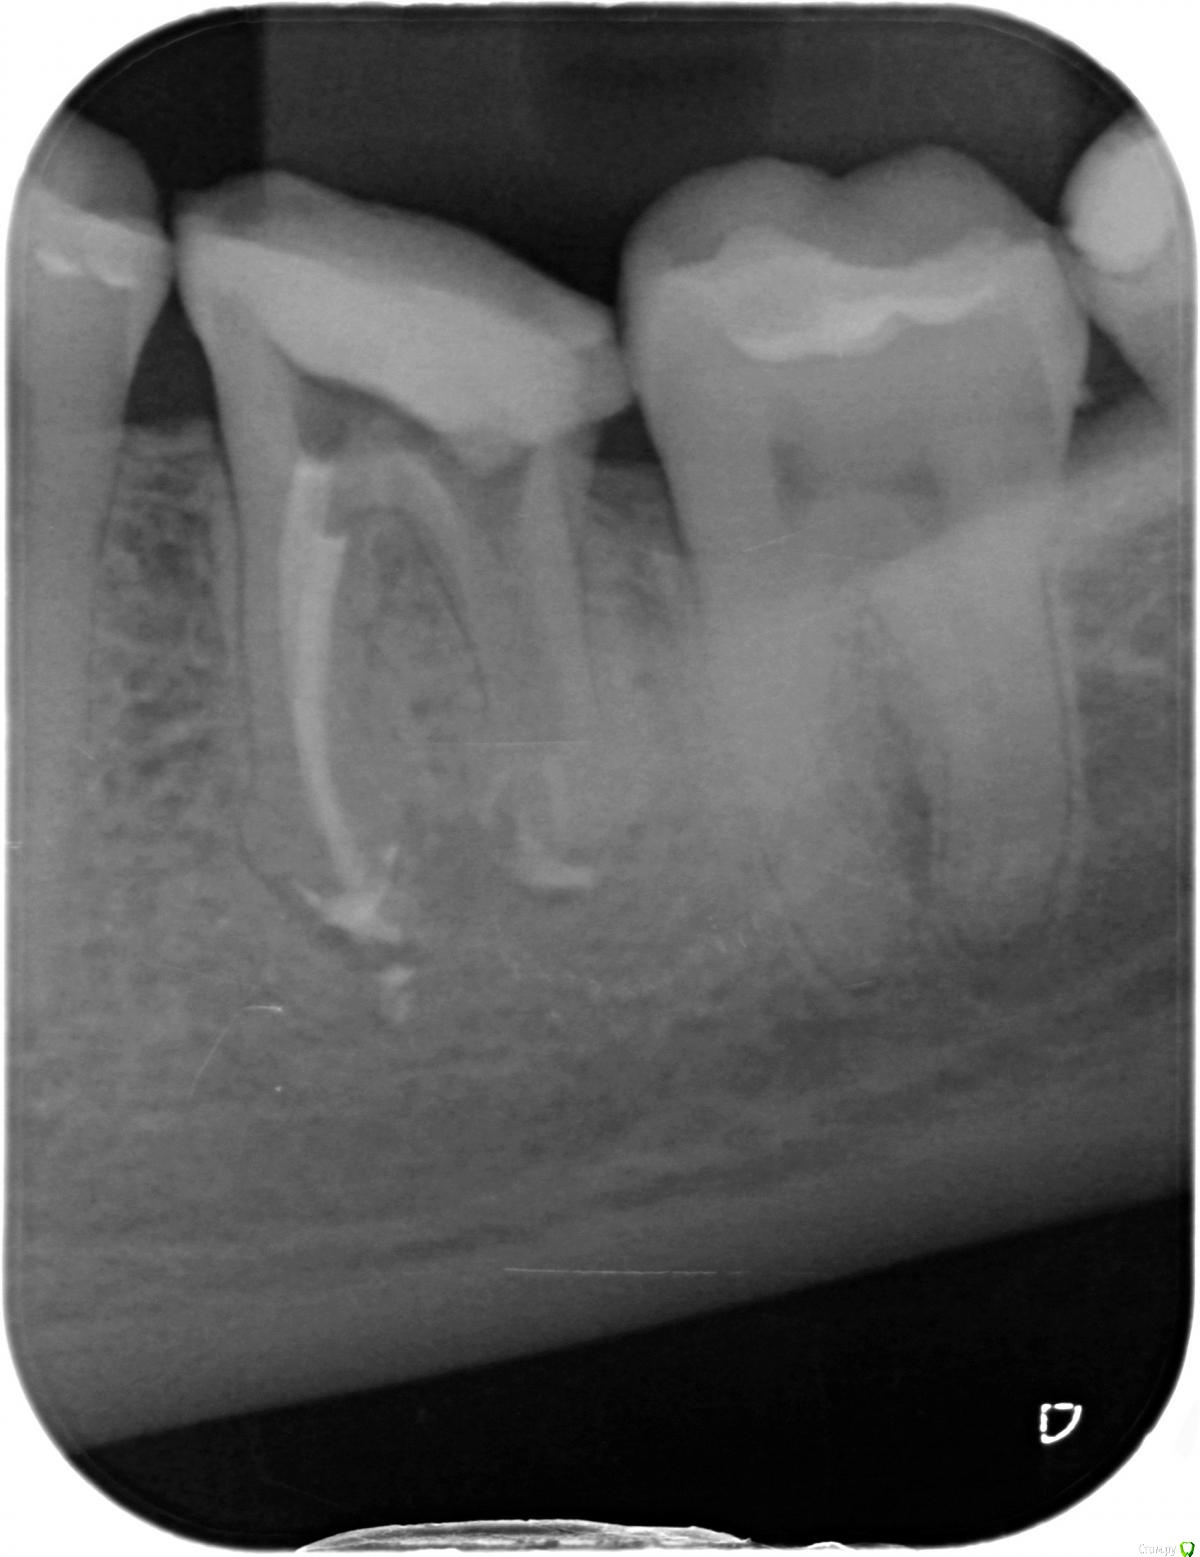

na_natali Опубликовано 5 июня, 2018 Поделиться Опубликовано 5 июня, 2018 Добрый день. Есть депульпированный зуб, обточенный под вкладку. В процессе подготовки зуба предположительно был перфорирован корень. Под временной пломбой зуб начал болеть, после открытия в канале обнаружена кровь.Предпринята попытка закрыть перфорацию. На снимке перфорация не визуализируется, место найти не удалось.Возможно, что зуб был поврежден в процессе подготовки, но непосредственно перфорации не было, а позже корень в истонченном месте треснул от нагрузки.На данный момент канал закрыт реставрирующим материалом и временной пломбой. Боль значительно уменьшилась, но присутствует при накусывании (слабовыраженная). Периодически появляются ноющие боли.Зуб закрыт на месяц - полтора, далее по ситуации. Если по истечении этого периода болей не будет,есть ли смысл ставить на него коронку? Мнения врачей разделились.Часть говорит что проще удалить и поставить имплант. Часть что установка коронки таки возможна.Снимки "до" и "после" прилагаю.Какие будут мнения? Ссылка на комментарий